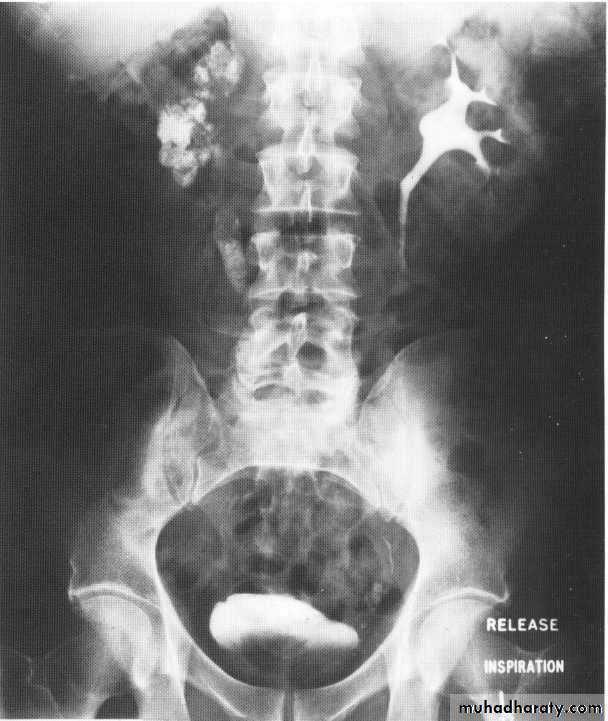

Obstructive uropathy

Causes 1.intralumenal .congenital like PUJ obstruction ,megaureter, Ureterocele (ectopic and orthotopic)Acquired : stones

Ivu FINDING OF ACUTE OBSTRUCTION

Increasingly dense ‘obstructive’ nephrogramModest kidney enlargement (50% of patients)

Delayed caliceal opacification

PCS and uretric dilation (g.1 mild PCS dilation ,g.2 moderate PCS dilation (blunting calyces),g.3 sever dilatation within thinning of parenchyma .

Spontaneous pyelosinus extravasations (up to 24% of patients

Large kidney(partial obstruction)

Small kidney (complete obstruction)